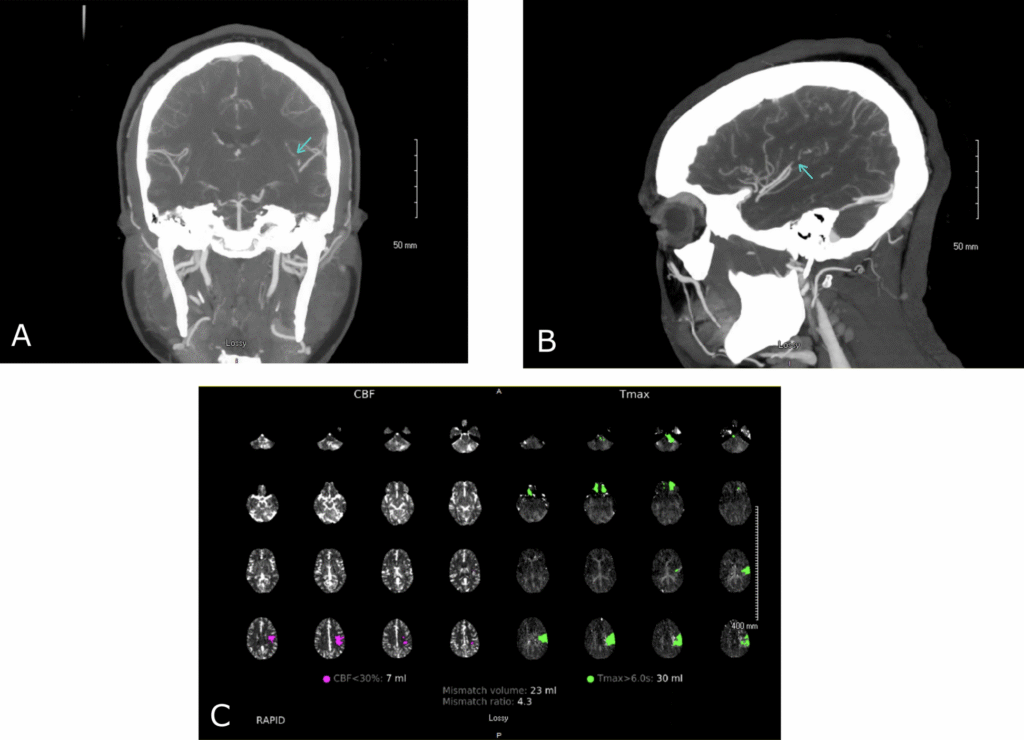

A recent case study has raised questions about the relationship between Epstein-Barr virus (EBV) infections and acute ischemic stroke (AIS) in young patients. The patient in question exhibited EBV-positive lymphoid proliferation, suggesting a potential connection with AIS, particularly due to her young age and lack of other significant stroke risk factors. Herpesvirus infections, including EBV, varicella zoster virus, and herpes simplex virus, have been implicated in the increased risk of ischemic stroke, notably in the pediatric and younger adult populations. Proposed mechanisms of this association include endothelial dysfunction, inflammatory cytokine release, and immune responses that may lead to vascular injury. Specifically, EBV may infect B lymphocytes, resulting in autoantibody production and potential coagulation issues that could elevate stroke risk.

While there have been isolated case reports of EBV-related strokes, comprehensive clinical trials on this topic remain scarce. Notably, a case described a 2-year-old girl developing an ischemic stroke related to EBV, characterized by elevated levels of inflammatory markers. Another case noted an adult suffering from brainstem hemorrhage due to EBV encephalitis, underscoring the virus’s potential to impact cerebral vasculature.

Given these insights, the report suggests that testing for EBV and other viral infections may be beneficial in young stroke patients lacking conventional risk factors. However, a definitive causal relationship remains uncertain, highlighting the need for further research in this area.